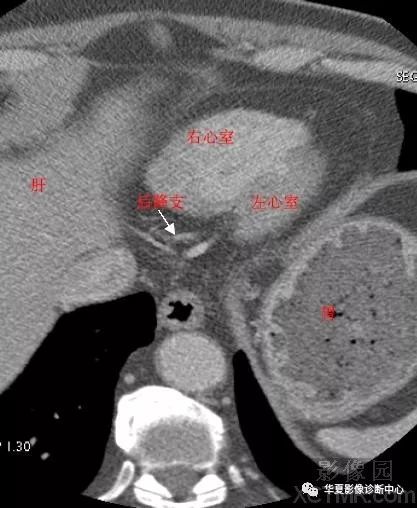

影像解剖|心脏冠状动脉ct解剖中文详细标注(图文)